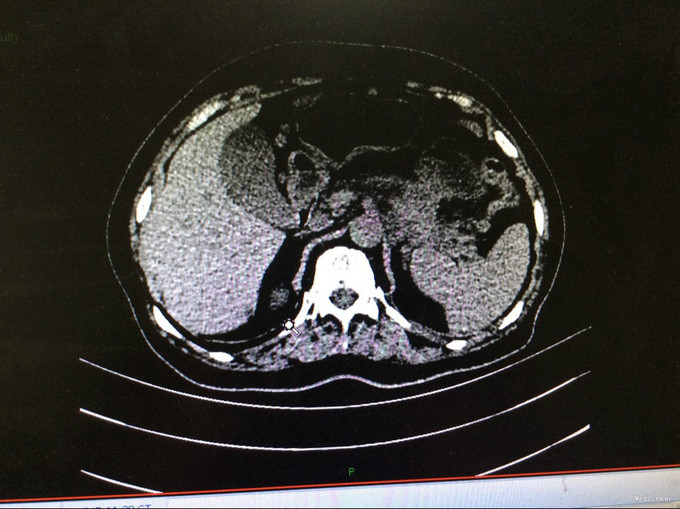

查体:生命体征平稳。神智清,查体合作,面容正常,淋巴结未触及肿大。双肺听诊呈清音,为闻及干湿罗音及哮鸣音;心率78次/分,律齐,无异常心音及心脏杂音;腹平软,肝脾肋下未及,未触及肿块,无压痛及反跳痛,肠鸣音正常。双下肢无水肿,生理反射存在,病理反射未引出。专科查体:无明显异常。辅助检查:湖北省中医院CT示:胰腺占位。CT检查示:1.结合原CT、MR检查,胰腺体尾部及周围异常改变,考虑胰腺炎伴坏死囊性变可能性大,与2015-11-20CT相比较,囊性病变略缩小;腹膜后淋巴结增多增大,大致同前;2. 所及肝脏多发囊肿;肝右叶后段其中一个病变边缘可疑强化,大小与前次相仿;3. 左侧肾上腺饱满。 MRI检查示: 胰腺体尾部及周围异常改变,考虑胰腺炎伴坏死囊性变可能性大,合并肿瘤性病变待排,病变累及腹膜伴腹膜后淋巴结增多增大,腹腔少许积液,请结合检查结果考虑;2. 所及肝脏多发囊肿;肝右叶后段其中一个病变边缘可疑强化,需鉴别于血管瘤与转移性病变,建议随访复查;3. 左侧肾上腺饱满;4. 所及右侧胸廓外小结节(层面16-7),直径约4mm,不除外右乳的病变:5. 所及腰椎骨性纵裂畸形。病理检查:(胰体尾部肿块穿刺组织)高分化腺癌,考虑为IPMN相关性浸润性癌。